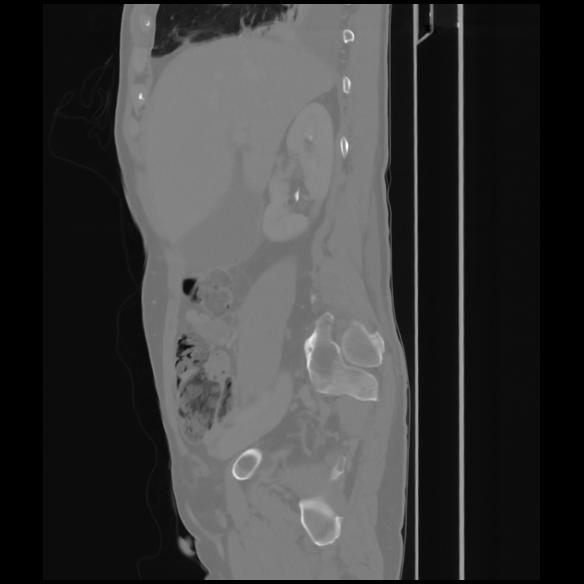

7 CUERPO,CE,Sagittal,3.000,CUERPO,Sagittal,